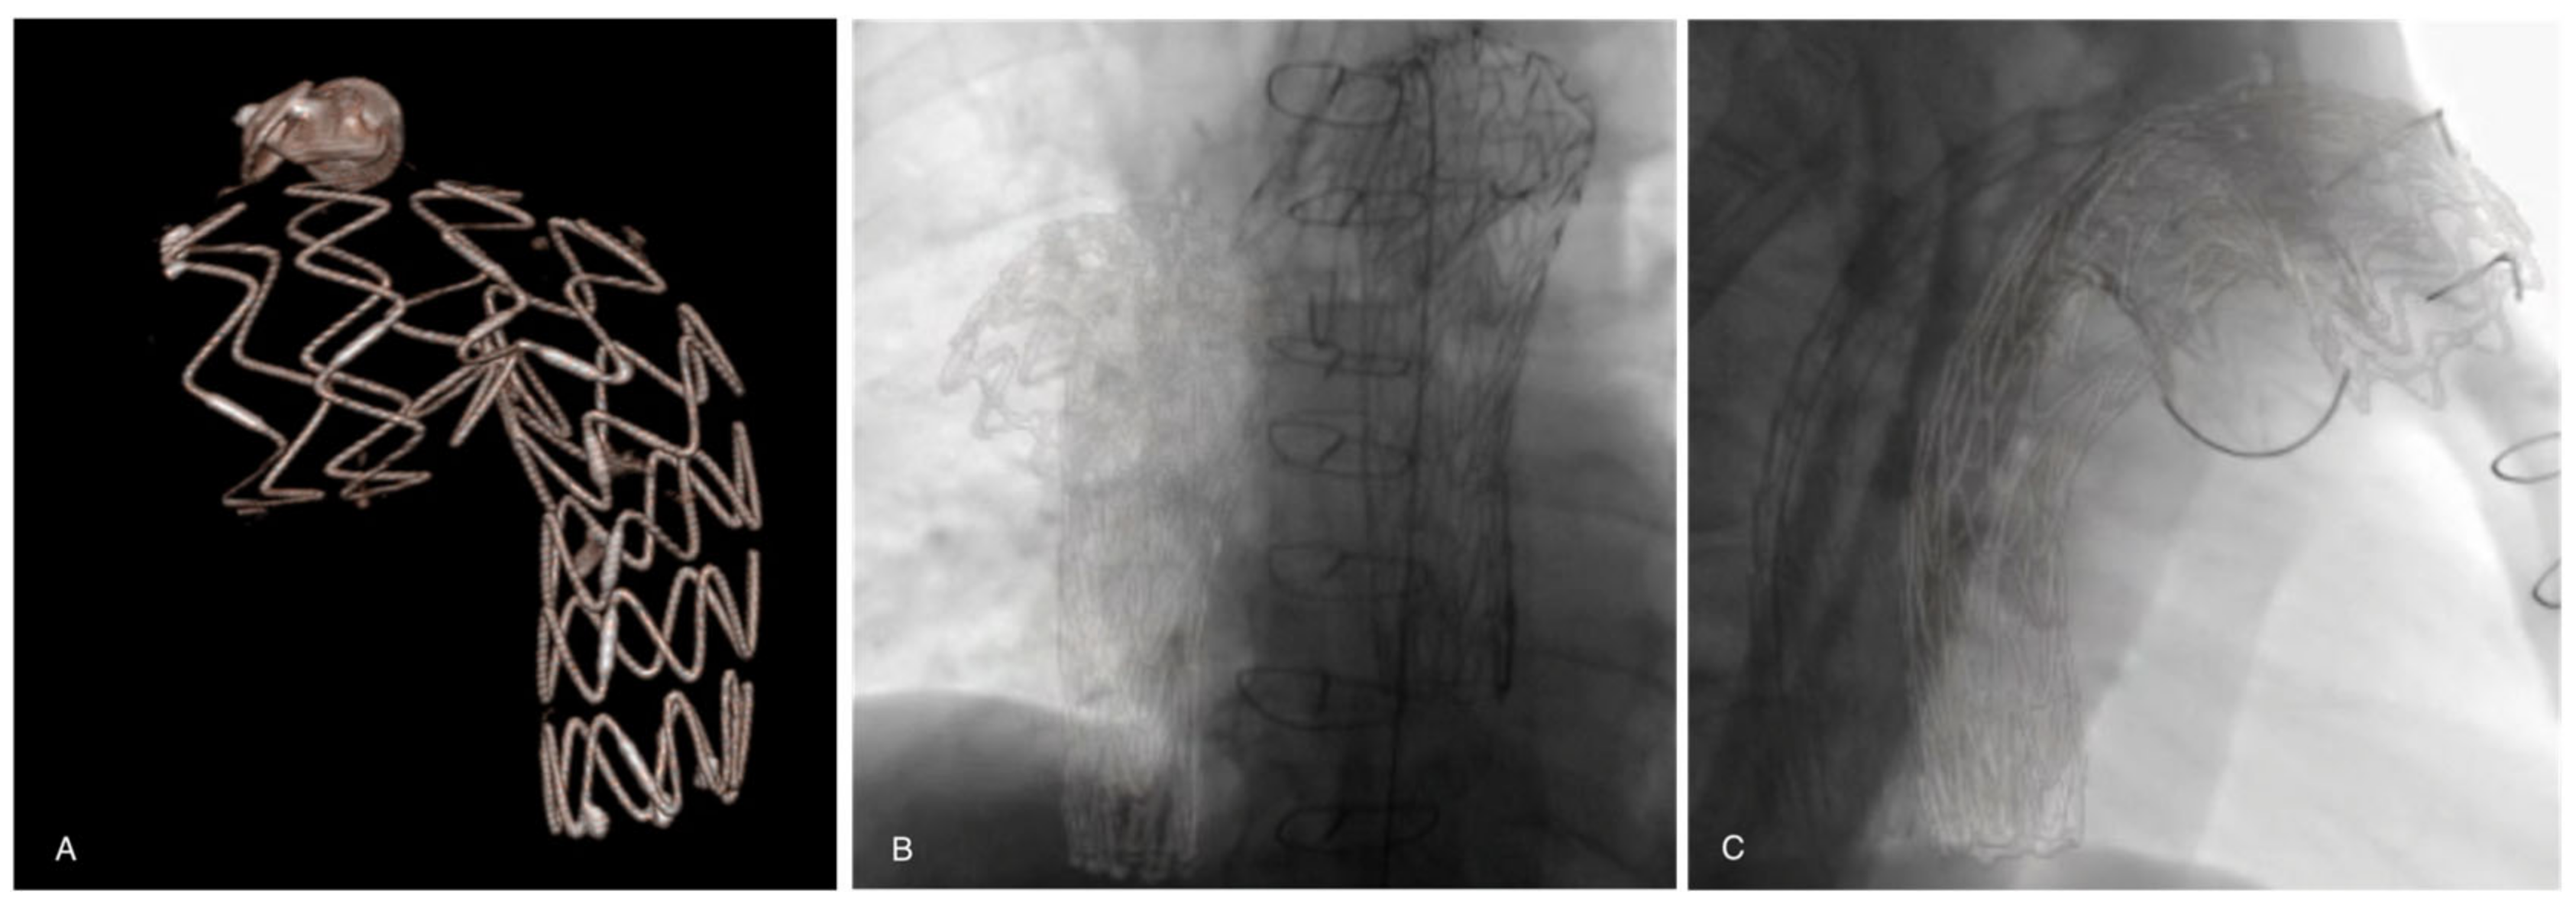

2. Materials and Methods

3. Results

4. Discussion